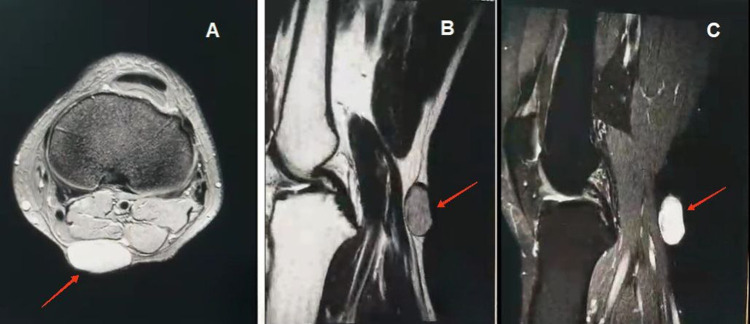

Case presentation: A 39-year-old male presented with popliteal swelling that had been present since 2016. It was not associated with pain or restriction of movement. On examination, the swelling was firm, well-capsulated, freely mobile, and not fixed to the underlying structure. There was no tenderness, warmth, or any signs of inflammation. The MRI revealed a 1.5×3 cm circumscribed subcutaneous lesion with low T1 and intermediate T2W signal, with normal adjacent joint structures. A total excision was performed, and the pathology report confirmed the diagnosis of epidermal inclusion cyst.